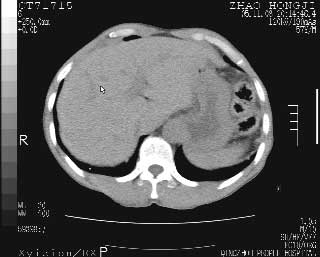

临床资料:男性,57岁,上腹部疼痛并5天,突然加重并延及全腹伴恶心5小时入院。胰淀粉酶化验在正常范围。检查:腹肌紧张,全腹压痛、反跳痛,尤以右上腹部为著。肠鸣音减低。血常规:wbc14.6x10/9, n:11.3x10/9 ,血压:135/90mmhg. 胸部透视:腹部肠腔轻度张气,未见其它异常改变。

肝缘见少许气体,胰尾部见少许气体包饶(蓝色圈),12指肠上部或球部邻近胆囊周边也可见少许气体影(黄色圈),并忖托出胆囊壁,12指肠远段肠道内未见明显气体(白色箭)。

肝脏前缘见少量积气、胰尾部见少许气体包饶,肾前筋膜未见增厚,临床淀粉酶不高,意见:上消化道穿孔。

入院3小时后行剖腹探查术,见腹腔内大量脓性混浊液约1000ml,十二指肠球部溃疡穿孔,溃疡面约2.5x2cm,穿孔直径约0.6cm。胃内容物外益,周围组织炎性水肿明显。行十二指肠穿孔修补术。术后诊断:

1、十二指肠溃疡穿孔

2、弥漫性腹膜炎

对于少量的腹腔游离气体,ct检查较普通透视有绝对的优势,它不仅可以看到肝脏前上缘的气体,而且还能够看到小网膜区的游离气体。从而可以肯定诊断。各位分析战友的很好,感谢大家的参入!